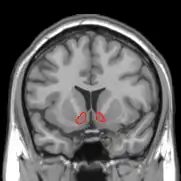

Researchers have also revealed an increased dopamine release in the nucleus accumbens. An experimental study with adolescent rats elucidated whether playful tickle can trigger dopamine release in the nucleus accumbens and whether the release of dopamine mediates positive emotions (Hori et al., 2013). In this study, 35- to 40-day-old rats received tickling stimulation for five minutes and light-touch stimulation for the same length of time. The marker for positive emotion was measured in ultrasonic vocalisations (USVs) as adolescent rats emit 50 kHz USVs as a symptom of positive emotion. The effect of tickling stimulation was then compared with light-touch stimulation, and the results revealed that tickling stimulation for five minutes significantly increased dopamine concentration in the dialysate of the nucleus accumbens (Hori et al., 2013). It also revealed that the 50 kHz USVs emitted during tickling are mediated by increased dopamine release in the nucleus accumbens (Hori et al., 2013).

The results of the study by Hori et al. (2013) have great implications for understanding the emotional effects that tickling evokes. The nucleus accumbens is a crucial part of the mesolimbic pathway, also known as the reward centre of the brain (Murrin, 2007). The neurons in the nucleus accumbens receive input from the dopaminergic neurons from the ventral tegmental area, and the mesolimbic pathway is driven by the dopamine release in this particular structure (Ikemoto, 2010). Dopamine plays an important role in regulating mood and behaviour and is a significant part of the brain's reward and pleasure centres (Sharot, Shiner, Brown, Fan, & Dolan, 2009). Dopamine is also associated with motivation, addiction, attention, and lust (Sharot et al., 2009). The evidence showing that tickling stimulation triggers dopamine release in the nucleus accumbens then suggests, despite engaging in a defensive reaction, tickling evokes positive emotions and is perceived by the brain as a rewarding and pleasurable experience. Thus, using tickling as an interactive play in the social setting may be useful in forming interpersonal bonds with others, both humans and animals, as the dopamine release that tickling triggers would result in positive emotions.